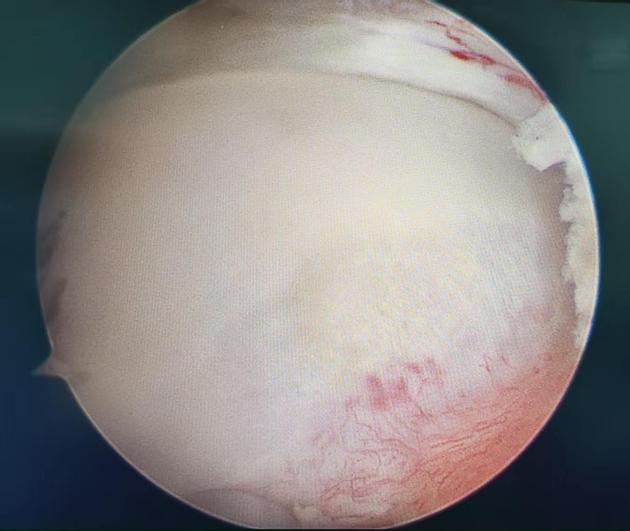

该病常伴随盂唇损伤,长期拖延会加重疼痛、加速关节退变。经充分评估与沟通,关节运动医学团队为王女士制定了微创、精准、快速康复的手术方案:关节镜下髋关节撞击股骨颈成形 + 盂唇修复术。经过术前检查,无手术禁忌,手术顺利开展,全程用时不到 1 小时。

4.镜下清晰视野,精准打磨增生骨质

5.完美修复损伤盂唇,重建髋关节正常结构

施此手术后,为王女士复查发现,髋部疼痛明显缓解,伤口微小、美观、出血极少,患者可早期下床,快速进入康复训练。